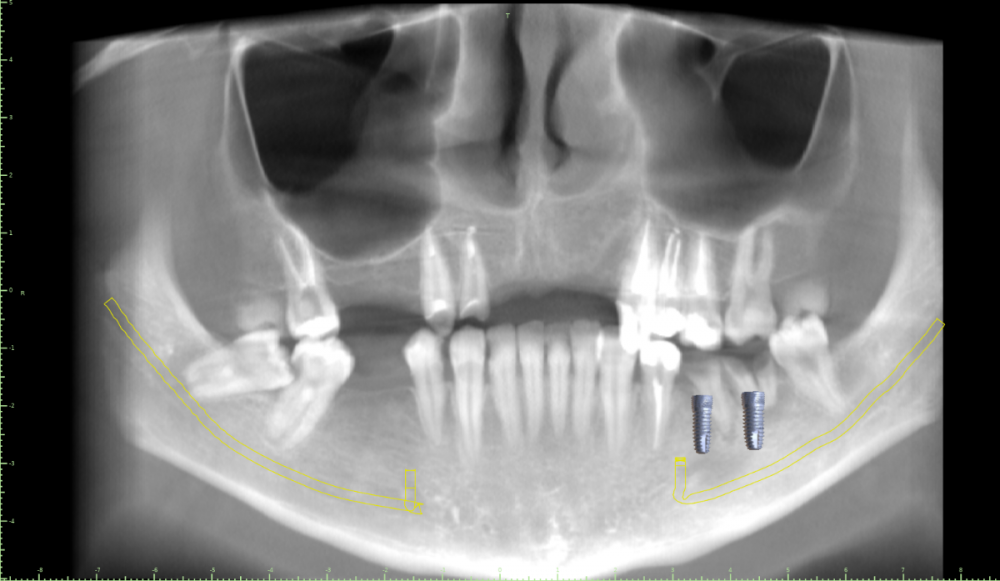

Женька Опубликовано 19 июля, 2021 Поделиться Опубликовано 19 июля, 2021 Коллеги, как решали бы ситуацию с толщиной? и решали бы вообще? Будет шаблон под пилотное сверление. 2.5 и 2.6 на ортоинтрузии в данный момент. Верх скорее всего бюгель будет. 4.8 удалю, 4.7 хотим апрайтинг сделать. Ссылка на комментарий

Irouil Опубликовано 19 июля, 2021 Поделиться Опубликовано 19 июля, 2021 По предоставленным снимкам отличные условия для имплантации Ссылка на комментарий

Женька Опубликовано 19 июля, 2021 Автор Поделиться Опубликовано 19 июля, 2021 @Евгений Ходыкин Глубже этого "перешейка" тонкого? планирую вот так Ссылка на комментарий

Женька Опубликовано 20 июля, 2021 Автор Поделиться Опубликовано 20 июля, 2021 @Irouil хотите сказать, что и решать тут ничего не надо? просто ставить и всё? Ссылка на комментарий

Irouil Опубликовано 20 июля, 2021 Поделиться Опубликовано 20 июля, 2021 Нет, решать есть чего, но не по хирургии, в основном. Решайте что с окклюзией будет, а костные условия предполагают «малоинвазивность») Только мягких тканей не забыть Ссылка на комментарий